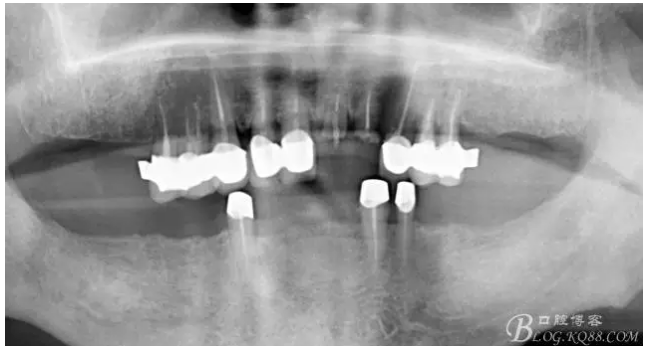

又囑咐病人半年復(fù)診一次,患者又過了兩年出現(xiàn)問題,再一次來到我們醫(yī)院,前牙咬螃蟹折斷了,我那個(gè)后悔啊,當(dāng)初要打了樁有多好,但是病人對(duì)我的信任,認(rèn)為咬硬物折斷是他的原因,只要給他修復(fù)上就好了

上牙出現(xiàn)了不同程度的牙齦萎縮

缺損太多 是必須用金屬樁修復(fù)的,

還要有足夠的牙本質(zhì)肩領(lǐng),大家現(xiàn)在可以看到患者的下頜套筒冠還是非常好的

雖然牙根折斷了,但是從這張片子可以看出我們的套筒冠還是很堅(jiān)挺的,有牙齦的退縮,但是牙槽骨致密程度非常好,值得欣慰